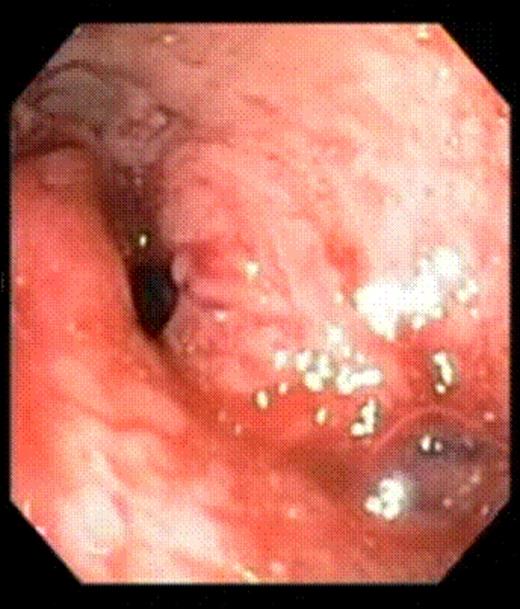

This 47-year-old man underwent a RYGB with a 30cc pouch, a 12mm circular stapled GJ and a 150cm long Roux limb in 2005. He lost 75kg with a reduction of BMI of 23.3 (63.7 to 40.4), achieving his lowest weight 3.25 years after his RYGB. The patient started experiencing dumping syndrome and regained 7kg in weight over the next 11 months, going up to a BMI of 42.5. An upper GI series x-ray showed an enlarged gastric pouch. An oesophago-gastro-duodenoscopy (OGD) showed a dilated GJ with loss of restriction. As an alternative to an open or laparoscopic revision, the patient elected to undergo endoluminal surgery using the StomaphyX™ device. The procedure was carried out under general anesthesia. An upper endoscopy was first performed to identify the anatomical landmarks of the pouch. The pouch length was noted to be 7 cm. The GJ was again observed to be widely dilated. The endoscope was then inserted through the shaft of the StomaphyX™ device, and the device and endoscope were introduced in tandem transorally into the pouch under continuous visualization. Once inside the pouch, vacuum was employed to draw large folds of gastric pouch wall tissue into the lumen of the device. With the gastric pouch wall on suction, the pouch wall was circumferentially plicated with serial firings of 6mm 3-0 polypropylene fasteners. This plication was in performed at two levels, one at 1 cm above the GJ anastomosis and one at 1 cm below the gastro-oesophageal junction. In total, 22 fasteners were delivered. A completion endoscopy was performed after the plication which showed that the 7-cm pouch had been reduced to 3 cm in length. The luminal diameter as well as the width of the GJ anastomosis was also significantly narrowed. The procedure took 40 minutes to perform with minimal intra-operative bleeding. There were no perioperative or postoperative complications.

Gastrojejunal stoma immediately after endoluminal gastric pouch plication